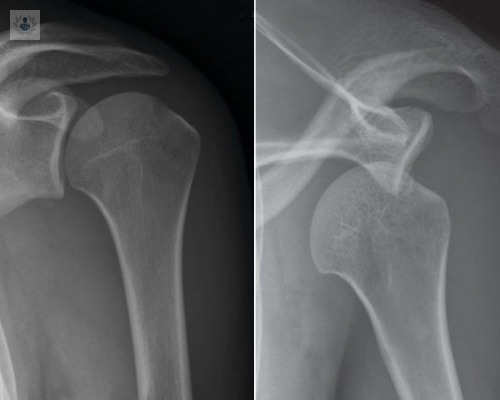

¿Qué es una Luxación de Hombro?

Una Luxación de Hombro es lo que se produce cuando coloquialmente decimos que el hombro “se ha salido de su sitio” debido a un traumatismo importante.

Luxación e Inestabilidad de hombro: Qué es y en qué consiste el tratamiento

La Luxación de Hombro es cuando la cabeza del húmero sale fuera de la cavidad donde se aloja normalmente en la escápula. Si la salida es completa se trata de una Luxación, y si la salida es parcial se trata de una subluxación. Ambas son las dos formas de Inestabilidad de la Articulación del Hombro.

Luxación de Hombro

El hombro es una articulación formada por una bola y una copa, que cuando se separa o disloca da lugar a una inestabilidad que puede ser completa o parcial.